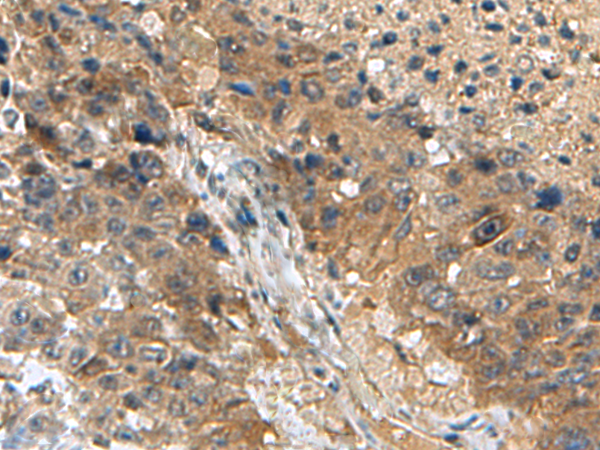

The image is immunohistochemistry of paraffin-embedded Human liver cancer tissue using (TPD52L3 Antibody) at dilution 1/140. (Original magnification: ×200)

The image is immunohistochemistry of paraffin-embedded Human esophagus cancer tissue using (TPD52L3 Antibody) at dilution 1/140. (Original magnification: ×200)